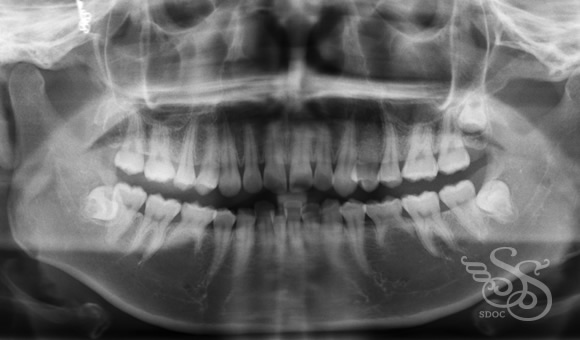

レントゲン:術後